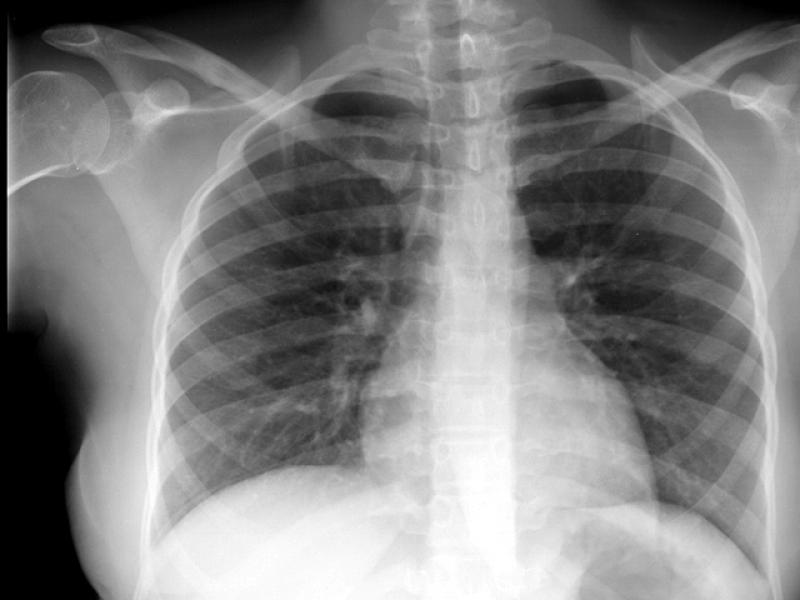

Impressora para Raio-x

RS IMPRESSORASUma impressora para raio-x deve ser específica para que haja o perfeito resultado, principalmente, se houver algum incoveniente que necessita de tratamento. Esse tipo de equipamento é...

Uma impressora para raio-x deve ser específica para que haja o perfeito resultado, principalmente, se houver algum incoveniente que necessita de tratamento. Esse tipo de equipamento é imprescindível em hospitais e clínicas.

Para uma peça de excelência, é de extrema autoridade contar com a ajuda de profissionais especializados e aptos a expandir um serviço de particularidade.

Deseja mais informações sobre impressora para raio-x?

Desenvolvendo um trabalho que oferece comodidade e certificando soluções inovadoras em outsourcing de impressão, a RS Impressoras é consolidada em seu segmento por conta da excelência apresentada em seus serviços.

Priorizando sempre as necessidades dos seus clientes, a empresa conta com uma equipe de profissionais elevadamente qualificados e aptos a expandir um serviço completo e de extrema particularidade.

Com experiencia a começar de 2007, a RS Impressoras garante a satisfação dos seus solicitantes, procurando sempre melhorias em cada um dos seus processos. Saiba mais entrando agora mesmo em contato!

Uma impressora para raio-x deve ser específica para que haja o perfeito resultado, principalmente, se houver algum obstáculo que necessita de tratamento. Esse tipo de equipamento é imprescindível em hospitais e clínicas.

Para uma peça de excelência, é de extrema seriedade contar com a ajuda de profissionais especializados e aptos a ampliar um serviço de particularidade.

Deseja mais informações sobre impressora para raio-x?

Desenvolvendo um trabalho que oferece comodidade e certificando soluções inovadoras em outsourcing de impressão, a RS Impressoras é consolidada em seu segmento por conta da excelência apresentada em seus serviços.

Priorizando sempre as necessidades dos seus clientes, a empresa conta com uma equipe de profissionais elevadamente qualificados e aptos a ampliar um serviço completo e de extrema particularidade.

Com experiencia doravante 2007, a RS Impressoras garante a satisfação dos seus solicitantes, procurando sempre melhorias em cada um dos seus processos. Saiba mais entrando agora mesmo em contato!